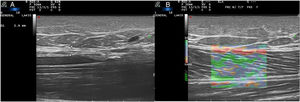

A 32-year-old woman presented with induration of the arms and the external aspect of the knees that had begun 3 months earlier and limited her movement (Fig. 1). Skin ultrasound (18-MHz linear probe, MyLab Class C, Esaote) revealed thickening of the muscular fascia, alterations of the echostructure of the superficial hypodermis, and a dermis with no pathological findings (Fig. 2A). Elastography showed increased stiffness of the muscle fascia (Fig. 2B). Based on these findings eosinophilic fasciitis (EF) was suspected, and was subsequently confirmed by nuclear magnetic resonance imaging and fascia biopsy. EF is a rare fibrosing disorder that manifests as pseudocellulitis (peau d’orange appearance), together with groove sign. Definitive diagnosis requires biopsy, which should include both the hypodermis and muscle fascia. Few articles have evaluated the diagnostic utility of ultrasound in EF. Ultrasound reveals an increase in the thickness of the muscular fascia, accompanied or not by alterations in the hypodermis. Elastography is a technique based on the detection of changes in tissue elasticity using ultrasound. Cutaneous ultrasound with elastography proved useful in guiding the diagnosis of this case of EF, and could potentially be used in follow-up to monitor treatment response.